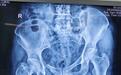

术后X线

患者郭某,中年女性,于今年5月25日车祸受伤,伤及左下肢及左骶尾部,就诊于当地医院行X线、CT检查诊断为:失血性休克、骨盆骨折、胫骨平台骨折、胫骨干骨折、全身多处损伤。入住当地医院ICU,经过输血、升血压等抢救,生命体征稳定后于5月28日转入我院。入院后紧急复查血常规、大生化、骨盆CT等相关检验检查,患者血红蛋白仍为70g/L(正常值为110-150g/L),骨盆左侧骶髂关节分离上移明显,右侧耻骨上下支分离移位,骨盆环严重变形。骨盆骨折是骨折中出血最多的骨折,可高达500-5000ml,成年人身体的血液大约在5000ml左右,此患者的血容量严重不足,张培良主任立即交代马上配血输血,行左下肢骨牵引,稳定生命体征。

经过一系列的检查及诊治,患者生命体征平稳,经过全科讨论,考虑病人多发骨折,病情严重,张培良团队确定微创复位固定手术方案,经过全面而细致的术前准备,于6月3日在全麻下行手术治疗,术中应用STARR骨盆复位架,仅需要2根螺杆(LC-Ⅱ通道、髋臼上横行通道)将骨盆固定于架子上,外加股骨髁上牵引,实现了骨盆的三维结构的控制,先将骨盆左右杆及前后杆解锁骨盆环,采用股骨髁上牵引将上移的骨盆牵回原来的高度,再用连在患者身体上的2根螺杆使之复位并维持,打入骶髂螺钉,使骨盆后环复位稳定,再借用原先复位骨盆的前后杆通道(LC-Ⅱ通道),打入Infix螺钉,稳定前环,这样就稳定了整个骨盆环。